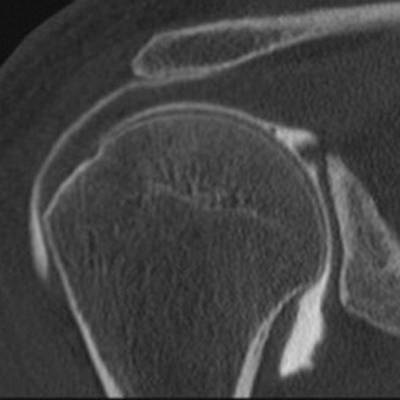

L’examen scanner de votre articulation (épaule, genou, cheville, poignet, coude, hanche) est réalisé après opacification de cette dernière par un produit de contraste iodé.

Cet examen permet une analyse précise du contenu de votre articulation (cartilage, ménisques, ligaments, coiffe des rotateurs, recherche de corps étrangers…) et éventuellement de procéder à une infiltration intra-articulaire de médicament à visée antalgique (le plus souvent un dérivé cortisonique).